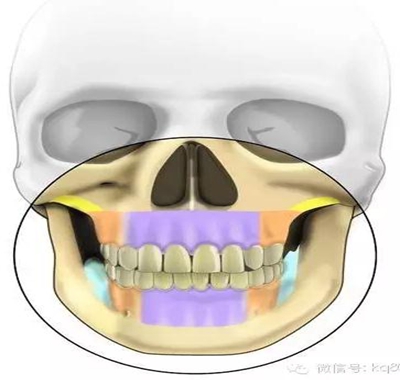

根據(jù)骨類型,骨密度,牙根間距、粘膜厚度不同,把上下頜分為不同區(qū)域,分別用紫橙藍黃四種顏色標記,這些區(qū)域就是傳統(tǒng)的可植入部位,每個部位所選擇的支抗釘也相應會有所差異